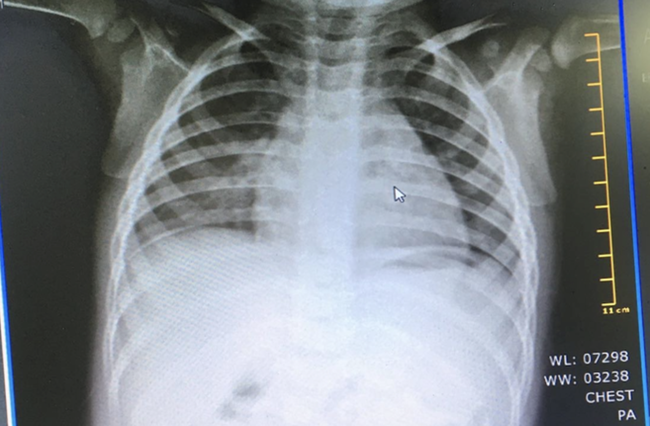

Các nhân viên y tế đã tiến hành chụp X - quang phổi, siêu âm cùng các xét nghiệm sinh hoá tại BV. Mẫu bệnh phẩm của bé được gởi khẩn đến Viện Pasteur TP.HCM để xét nghiệm PCR.

Ngày 21/2, Kết quả xét nghiệm cho thấy bệnh nhi âm tính với Covid-19.